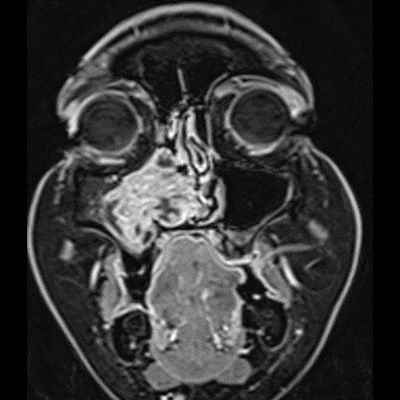

- A) Koronal T2 ağırlıklı görüntülerde sol maksiller sinüs lümenini dolduran, belirgin ‘convoluted’ (karmaşık-kıvrımlı) serebriform patern sergileyen lezyon (oklar), kontrastlı seride heterojen ve yoğun kontrastlanma göstermektedir (oklar). Perfüzyon incelemesinde pedinkülünde perfüzyon artışı gösterdiği, diğer kontrastlanan segmentlerin nispeten hipoperfüze olduğu görülmektedir (ok).

- B) BT incelemesinde maksiller sinüsün duvarları özellikle lateralde daha belirgin olmak üzere reaksiyonel kalınlaştığı izleniyor (oklar). DWI ve ADC haritasında lezyonda belirgin bir kısıtlılık görülmemektedir (oklar).

- MR incelemesinde sinonazal inverted papilloma tipik olarak T2 ve post-kontrast T1 serilerde ‘convoluted’ serebriform paternde heterojen sinyal ve kontrastlanma gösteren, pedinküler orijininde daha belirgin perfüzyon artışı sergileyen, genellikle difüzyon kısıtlaması izlenmeyen ve komşu sinüs duvarlarında ekspansiyona bağlı remodelinge yol açabilen benign ancak lokal agresif karakterde bir yumuşak doku kitlesi olarak izlenir.